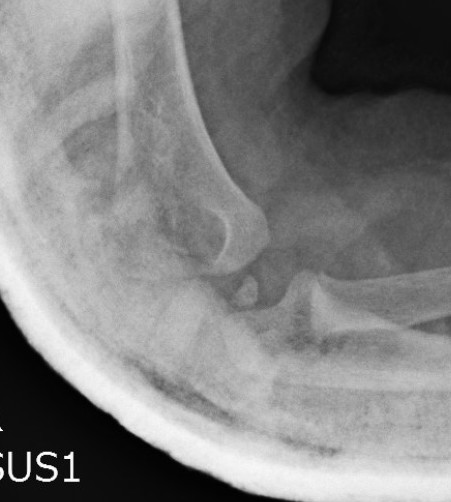

Ultrasound

Arthrogram

Closed reduction +/- percutaneous K wires

- 10 cases of transphyseal humeral separation in neonates

- birth trauma

- 4 closed reduction, 6 percutaneous K wire

- all healed, no deformity or functional loss

Cha et al Injury 2020

- 12 patients treated with arthrogram + K wire fixation

- normal outcomes, no AVN

May need arthrogram to visualize distal humerus epiphysis